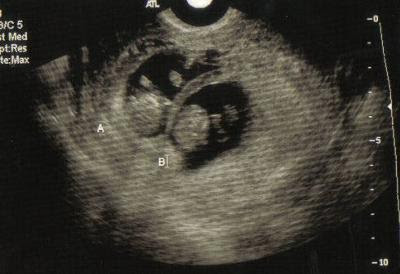

Ultrasound Scan Of 10 Weeks Old Twins Stock Photo Image Of Women Human

Week 10 Ultrasound Duke Twins

Twins 2 Gestational Sacs 10 Weeks Critical Care Sonography

Twins At 10 Weeks 2 Days